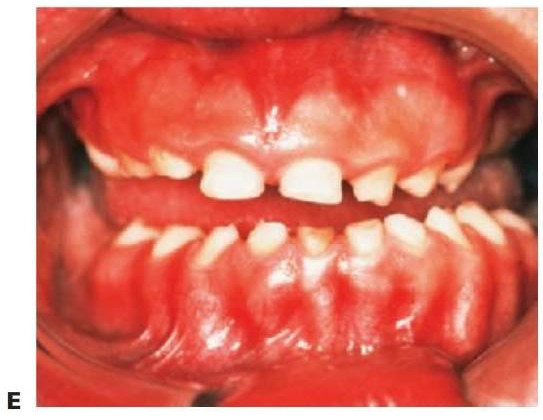

Displasias ectodérmicas

La displasia ectodérmica describe un grupo de trastornos del desarrollo que con frecuencia son heredados y afectan a las estructuras derivadas del ectodermo, como el pelo, los dien tes, las uñas, la piel y las glándulas sudoríparas. La forma más común es la forma hipohidrótica ligada al cromosoma X (OMIm305100, EDA1, Xq12-q13.1 [brazo corto del cromosoma X]). En este trastorno, la presentación usual es la de un niño varón con:

- Varios dientes ausentes (fig. 9.1 B).

- Cabello fino y ralo (fig. 9.2A, B).

- Piel seca (fig. 9.2A).

- Hipoplasia maxilar.

- Eversión de los labios.

- Pigmentación alrededor de la boca y los ojos.

Los dientes son pequeños y cónicos y a menudo presentan un gran diastema anterior (fig. 9.3). Sus manifestaciones pueden limitarse a un solo diente ausente o a un incisivo lateral en clavija (v. hipótesis de Lyon, más adelante) y las mujeres heterocigóticas suelen ser diagnosticadas gracias a este tipo de dentición.

Tratamiento

El objetivo del tratamiento es proporcionar una función adecuada, mantener la dimensión vertical y restaurar el aspecto estético. La mejor opción desde el punto de vista de las consideraciones sociales es el inicio del tratamiento a los 2-3 años de edad. Sucede a menudo que los padres pretendan con ahínco «normalizar» el aspecto del niño. Un primer paso suele ser la colocación de restauraciones de composite para enmascarar el aspecto «similar a un colmillo» del diente anterior caniniforme (fig. 9.3A). Más adelante se efectuará la provisión de prótesis para que sufra menos burlas, sobre todo en el momento en que el niño empieza a ir a la escuela. La prótesis puede prepararse tan pronto como al niño se le puedan tomar impresiones, pero la realidad es que el primer juego de prótesis suele llevarse en el bolsillo y a medida que el niño crece se desarrolla el deseo de tener un aspecto más normal. Gracias a una incentivación y refuerzo positivo del niño, la mayoría de los niños llevarán puestas sus prótesis.